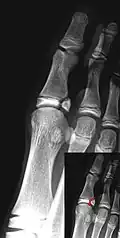

Salter–Harris I fracture of distal radius. -